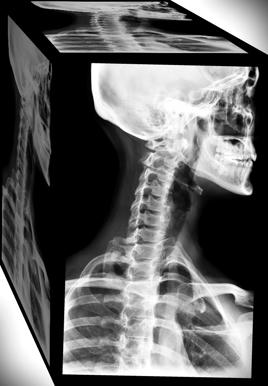

Isis fue conducida al hospital Barra D’Or, en la Av. Ayrton Senna, 2541 - Barra da Tijuca - Rio de Janeiro, donde fue atendida por la fractura de una de sus primeras vertebras, la C1. Tras el accidente el asesor personal de la actriz diría que "Ella tiene una vértebra rota, pero está bien y está siendo medicada", mientras que la joven diría luego a los medios que "Estoy mejorando. Prácticamente nací de nuevo. Dios ha sido generoso conmigo". Isis debió permanecer hospitalizada por un breve tiempo, tras lo cual se informó que fue dada de alta con evolución favorable y con un collarín cervical.

La lesión que sufrió Isis Valverde en su columna, es descrita medicamente como “Una fractura cervical es la rotura de una o más de las siete vértebras cervicales (huesos) en el cuello. Las siete vértebras cervicales son llamadas C1 a C7. Las vértebras cervicales sostienen la cabeza y permiten que el cuello se doble y gire”. La vertebra C1 llamada también Atlas, une la cabeza al cuello.

“Las lesiones de C1 - C2 pueden comprometer la vida del paciente y producir tetraplejia, por lo que son de extraordinaria gravedad”, “La lesión medular cervical es tan grave, que presenta entre un 7 y un 15% de mortalidad general y entre un 35 y un 50% de mortalidad en las lesiones cervicales completas, según diferentes publicaciones”.